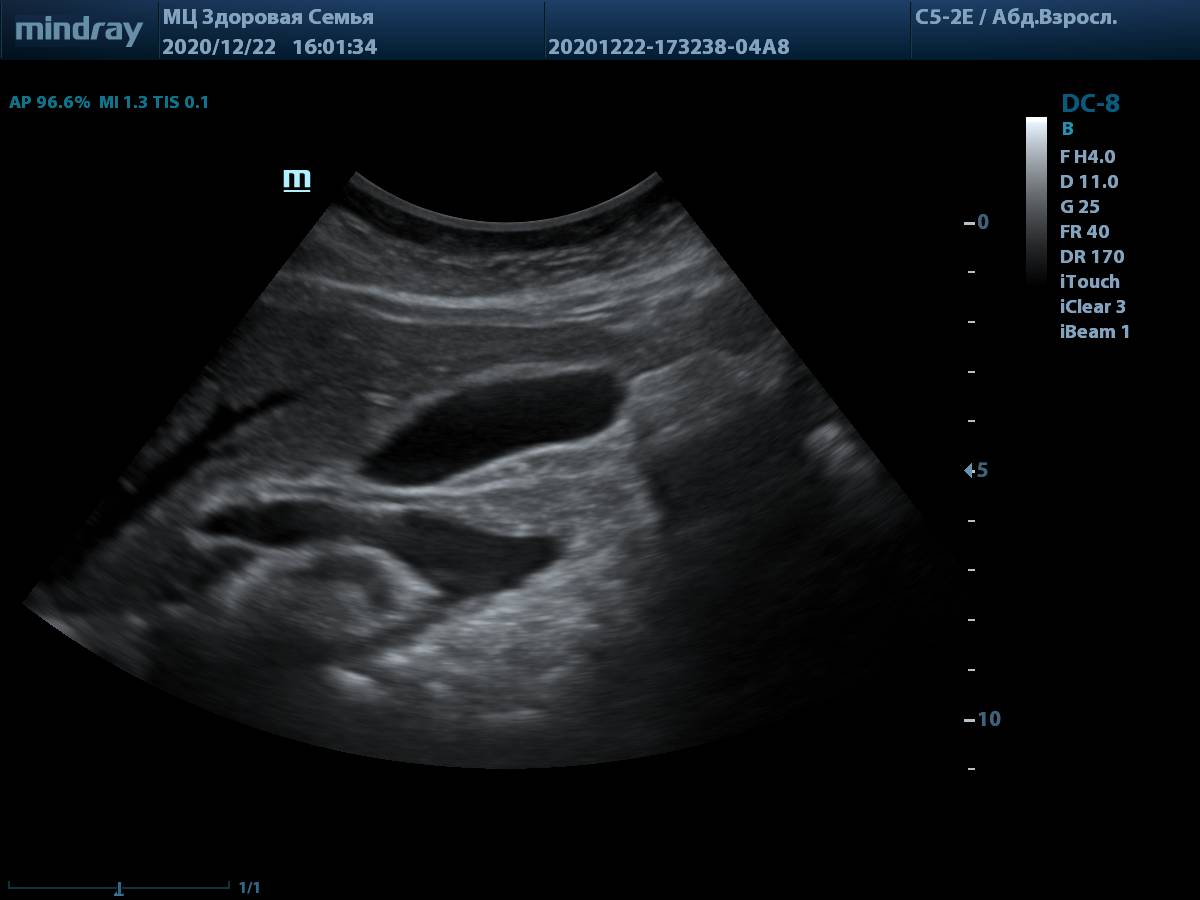

6. Пример визуализации ворот печени у пациента с избыточной массой тела. Четкие контуры холедоха и портальной вены, идеально для проведения измерений.